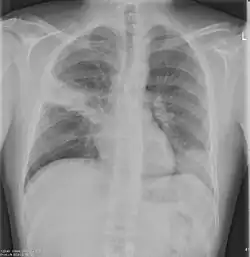

Chest X-rays and X-ray computed tomography (CT) can reveal areas of opacity (seen as white), indicating consolidation.[14] CAP does not always appear on x-rays, sometimes because the disease is in its initial stages or involves a part of the lung not clearly visible on x-ray. In some cases, chest CT can reveal pneumonia not seen on x-rays. However, congestive heart failure or other types of lung damage can mimic CAP on x-ray.[16]

When signs of pneumonia are discovered during evaluation, chest X-rays and examination of the blood and sputum for infectious microorganisms may be done to support a diagnosis of CAP. The diagnostic tools employed will depend on the severity of illness, local practices and concern about complications of the infection. All patients with CAP should have their blood oxygen monitored with pulse oximetry. In some cases, arterial blood gas analysis may be required to determine the amount of oxygen in the blood. A complete blood count (CBC) may reveal extra white blood cells, indicating infection.

Chest X-rays of a CAP patient before (left) and after treatment

CAP is treated with an antibiotic that kills the infecting microorganism; treatment also aims at managing complications. If the causative microorganism is unidentified, which is often the case, the laboratory identifies the most effective antibiotic; this may take several days.

Ceftriaxone and azithromycin are often used to treat community-acquired pneumonia, which usually presents with a few days of cough, fever, and shortness of breath. Chest x-ray typically reveals a lobar infiltrate (rather than diffuse).[20]